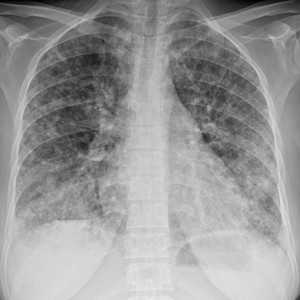

Как выглядят метастазы в легких на рентгене? Слева — узловые образования у пациента с раком яичка. Справа - метастазы рака яичников гематогенного характера с выраженным опухолевым лимфангиитом (обратите внимание на деформированный сетчатый, линейный характер легочного рисунка).